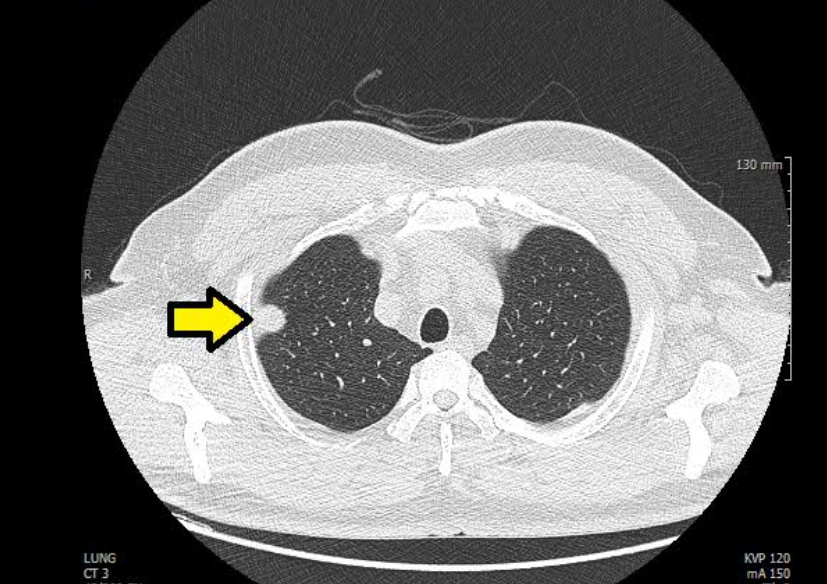

흉부 엑스레이로 나타나는 것

엑스레이 결과지를 받으면 처음엔 알아보기 어렵지만, 구조적으로는 규칙이 있어요. 폐는 공기로 가득해 검게 보이고, 심장은 가운데 밝게 자리하죠. 만약 폐 안에 뿌연 부분이 생기면 염증, 액체, 혹은 출혈을 의심하고, 반대로 너무 까맣게 보이면 기흉일 수 있어요.

의사들은 ‘폐야, 심장이야, 갈비뼈야’ 하며 차근차근 확인합니다. 심장이 커져 있으면 고혈압이나 심부전의 가능성을 생각하고, 횡격막이 들려 있으면 공기나 가스가 차 있을 수 있어요. 또 갈비뼈가 부러졌거나 척추가 휘어져 있으면 엑스레이에서도 바로 드러납니다. 이처럼 단 한 장의 사진에도 온몸의 이야기가 담겨 있는 거예요.